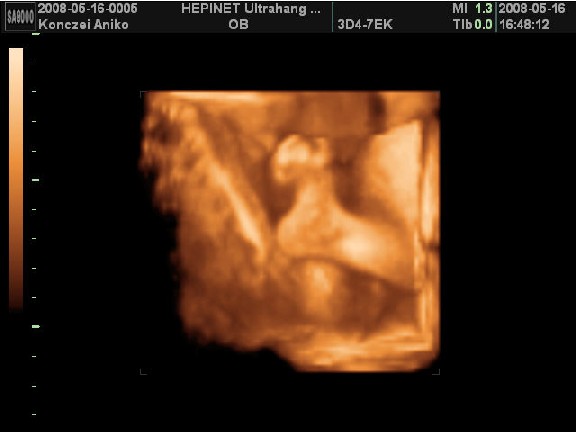

Voltam már uh-n 3x. Az elsőn 6 hetesen, mert barnáztam akkor 2 napig, majd 2 hét múlva is egy napig...A következő 10hetesen volt, mert már nem bírtam magammal, tudni akartam, h minden ok odabent. És végül a 12 hetes uh 12+3-on..ekkor minősítették 16+6-ra. A nemét még nem tudjuk, de nagyon kiscsajt szeretnék...hát majd kiderül. Most hétvégén majdnem elrohantam 4D-re, mert ismét nem bírok magammal...de szerencsére fullon voltak, meg a nő amúgyis le akart beszélni a 4D-ről, mondván csak 24hét után érdemes...szép. Így mostmár úgy döntöttem, hogy inkább kivárom a 3 hetet, amikoris hazalátogatok 5 napra. Jún. 5-én fogok elmenni 4D-re otthon, ahol kb 1/4-be kerül. Ja és nem fogjátok elhinni, de itt azért is külön fizetni kell, hogy a nemét megmondják.